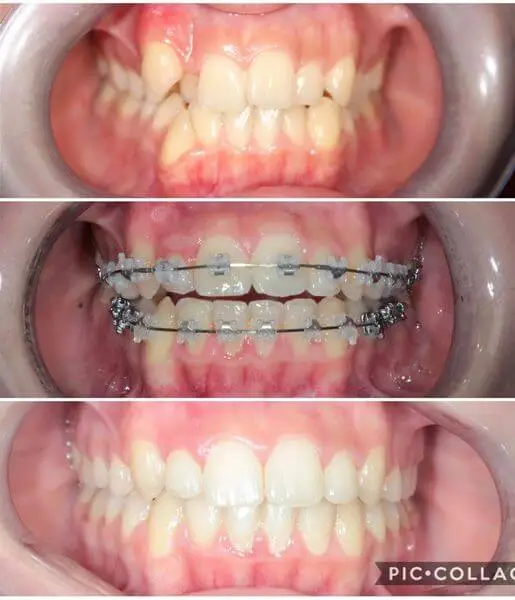

Fogszabályozás és direkt héj

Dr. Csulak Fruzsina fogszabályozó szakorvos és Dr. Bakonyi Panna fogszakorvos közös munkájának eredménye ez a gyönyörű mosoly.

Kedves Páciensünk erősen torlódott fogsora miatt keresett fel minket. Fém Damon önligírozó készülék került fel az alsó és a felső fogívre is, 3 hónap különbséggel. Az alsó fogív fogszabályzása jelenleg is tart. A felső készüléket közel 1,5 év után távolítottuk el.

A levételt követően Dr. Bakonyi Panna direkt héjakkal tette még ragyogóbbá Páciensünk mosolyát.